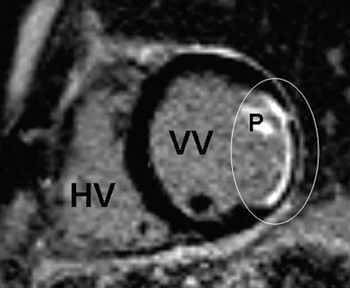

Det foreligger derfor et behov for en ikke-invasiv diagnostisk metode for å diagnostisere myokarditt og for å vurdere prognosen og effektiviteten av behandlingen. Hjerte-MR med kontrast er godt egnet til å diagnostisere myokardskade forårsaket av både akutt og kronisk myokarditt (8). Myokardskaden ved myokarditter har en karakteristisk epikardial utbredelse og følger ikke forsyningsområdet til koronararterier. Dette er i motsetning til myokardinfarkter, som alltid har en dominerende subendokardial utbredelse. Områder med kontrastopptak ved hjerte-MR korrelerer godt med aktiv myokarditt ved histopatologisk undersøkelse (6). I tillegg gir MR av hjertet informasjon om hjerte- og perikardfunksjon.

Kontrastbasert MR vil kunne avdekke uoppdaget gjennomgått myokardinfarkt, slik som vi fant hos en av pasientene som hadde angiografisk normale koronararterier. Ved myokardinfarkt på grunn av en okkludert koronararterie vil alltid kontrastoppladningen følge distribusjonsområdet til koronararterien og være subendokardial med varierende grad av transmuralitet (fig 2). Ved myokarditt vil kontrastoppladningen være epikardial og ikke følge koronararteriens forsyningsområde (fig 3). Det kan oppstå vansker med diagnostisering av myokardskade på grunn av myokarditt i forhold til myokardskade på grunn av myokardinfarkt dersom det samme området av myokard er rammet.